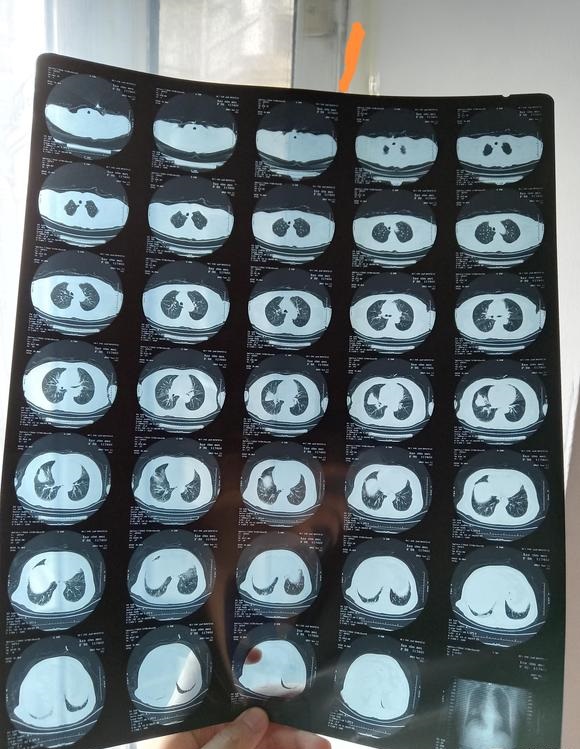

北港永下 02021-12-21 患者家属我父亲体检时发现有肿块。到人民医院检查结果显示食管囊肿或支气管囊肿本来医生说不是很大的手术。几天前做了增强ct。又说有可...